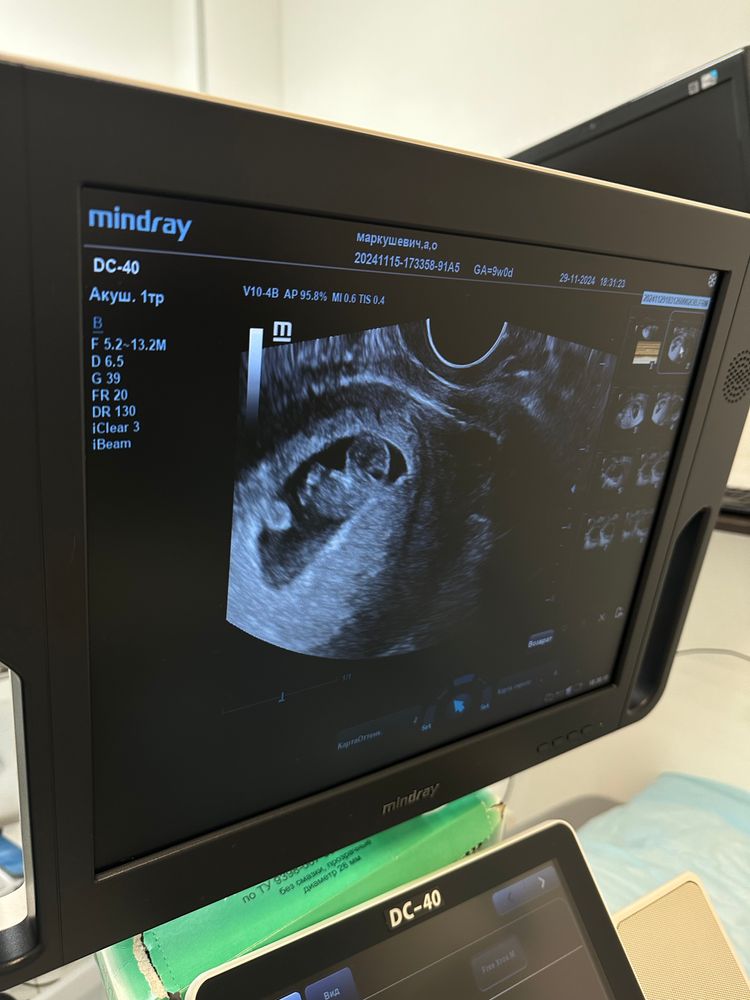

Была на узи, срок ровно 9 недель, по ктр совпадает, ктр 22.5, а вот свд 30, врач сказала все замечательно

вчера тоже делали узи ( попросили перед учетом свежее узи), там пя было 47мм, но не понравились выражения врача, что у вас наименьшайший ктр ( у неё вышло 17) и что у меня есть отслойка, угроза и прочее ( сегодня ничего подобного не нашли)

по фото в

роде ему не тесно…

Сегодня переделывала, так как вчера мне другой врач сказал, что все плохо и у меня чуть ли не выкидыш скоро будет , сегодня ничего такого не увидели , только вот смутило, что свд 30, а ктр 22

Алёша, ну по фото смотрю и вроде ему там не тесно, видела сегодня как шевелится